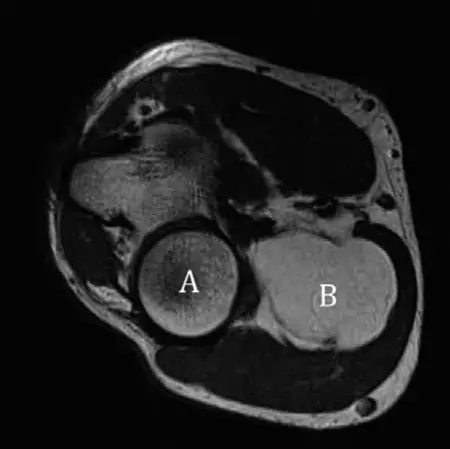

الرنين المغناطيسي (MRI) :

- هو المعيار الذهبي لتقييم أورام الأنسجة الرخوة، خاصة الكتل العميقة أو الكبيرة.

-

يوفر تفاصيل ممتازة للأنسجة الرخوة، مما يسمح للأستاذ الدكتور محمد هطيف بتقييم:

- حجم الورم وموقعه الدقيق : وعلاقته بالعضلات، الأعصاب، الأوعية الدموية، والعظام.

- مكونات الورم : هل هو دهني بالكامل؟ هل يحتوي على مكونات صلبة غير دهنية؟

- السبتات الداخلية (Internal Septations) : وجود حواجز داخلية سميكة (>2 مم) أو عقدية أو معززة بالصبغة داخل كتلة دهنية يثير الشك بقوة في الساركوما الشحمية اللانمطية (ALT) أو الساركوما الشحمية جيدة التمايز (WDLPS).

- التعزيز بالصبغة (Enhancement) : زيادة إشارة الورم بعد حقن الصبغة الوريدية تشير إلى وجود مكونات غير دهنية أو زيادة في الأوعية الدموية، وهو أمر مقلق.

- الوذمة المحيطة بالورم (Perilesional Edema) : التورم حول الورم قد يكون علامة على ورم خبيث.

- لا يمكن للرنين المغناطيسي وحده دائمًا التمييز بشكل قاطع بين الورم الشحمي الحميد والساركوما الشحمية جيدة التمايز، ولكنه يوجه الحاجة إلى الخزعة.